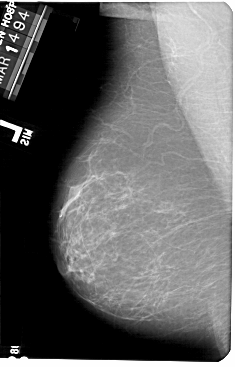

A_1182_1.RIGHT_MLO

RIGHT_MLO LINES 5491 PIXELS_PER_LINE 3421 BITS_PER_PIXEL 12 RESOLUTION 43.5 OVERLAY